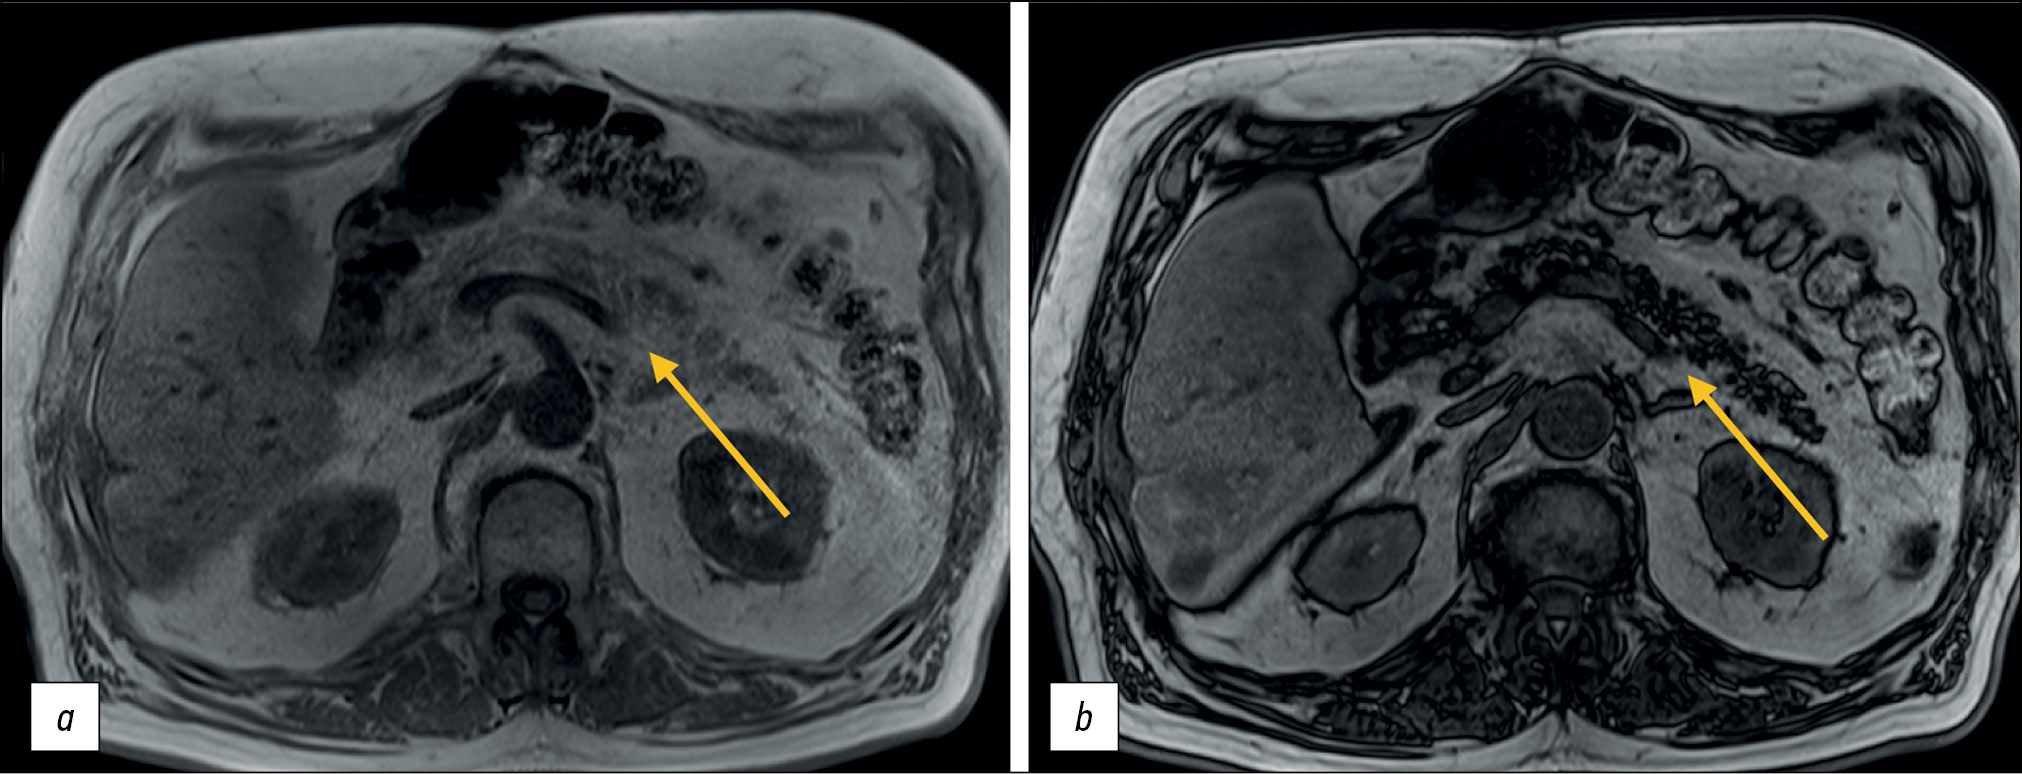

For a more accurate assessment of hepatic steatosis or signs of hemochromatosis, in-phase and opposed-phase T1-WIs should also be included in the standard MRI protocol. Furthermore, this sequence is useful in the diagnosis of adrenal adenoma (Fig. 6), clear-cell renal cell carcinoma, and pancreatic fatty infiltration (Fig. 7). These sequences must be obtained before contrast agent injection. Out-of-phase images allow for the assessment of signal loss from adipose tissue and fat-containing lesions such as liver adenomas or hepatocellular carcinoma. Moreover, the determination of the proton density fat fraction is the gold standard for noninvasive quantitative assessment of hepatic steatosis. However, this sequence is not included in the routine protocol.

Figure 6. Abdominal computed tomography, axial plane (а): a right adrenal mass of nonuniform density is visualized (arrow); abdominal magnetic resonance imaging (b, с), in-phase (b) and opposed-phase (с): a typical signal loss from the adenoma fat component in the opposed-phase is detected (arrows).

Figure 7. Abdominal magnetic resonance imaging, pancreatic lipomatosis (arrows): а in-phase, b opposed-phase. In the opposite phase, a signal loss from the pancreas with a normal signal from the liver is detected.